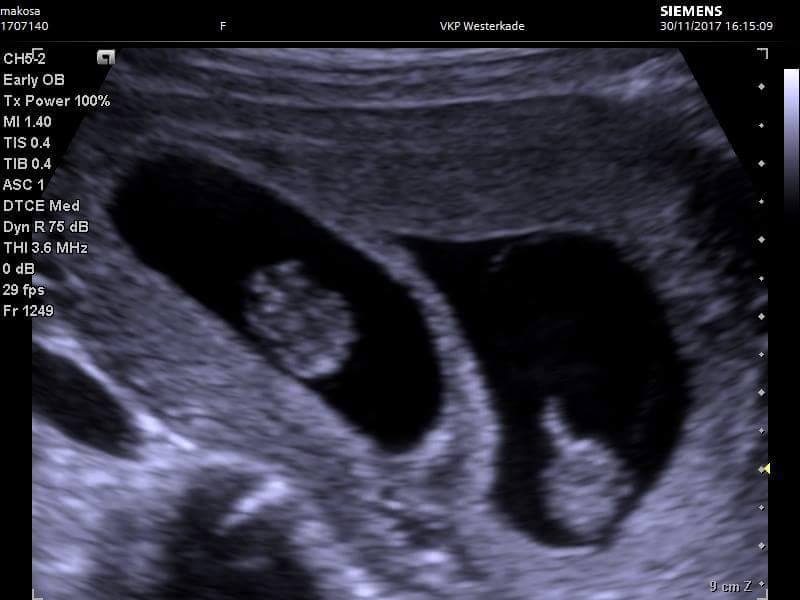

No wlaśnie tego dowiem się dopiero 18.12 dlatego tak się martwię. Poza tym jeden kropek jest mniejszy i powiedzieli mi, że to niedobrze... Tego 18.12 wszystkiego sie dowiem i może się trochę uspokoje. Na zdjeciu z USG wyglada to nawet dobrze, jak 2k2o, ale nikt mi tego oficjalnie nie potwierdził. (Mieszkam w Holandii i tutaj się trzeba naczekać na te wizyty)

Załączniki

• received_2050592821633989.jpeg

received_2050592821633989.jpeg

38,2 KB · Wyświetleń: 160